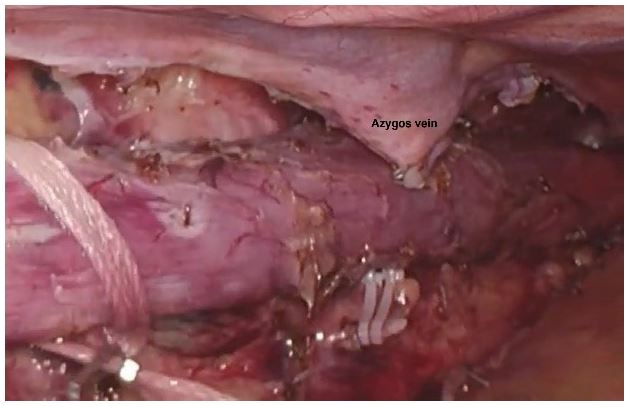

The patients were divided into two groups based on whether the arch of azygos vein was preserved (Preservation group/AVP) (Figure 1) or transected (Transected group/AVT) (Figure 2). During esophageal mobilisation, the azygos vein was either suture-ligated, clipped (using a hem-o-lok) or divided using a laparoscopic stapler with a vascular cartridge in the Transected group.

Figure 1: Azygos vein preserved.

Figure 2:Azygos vein transected.